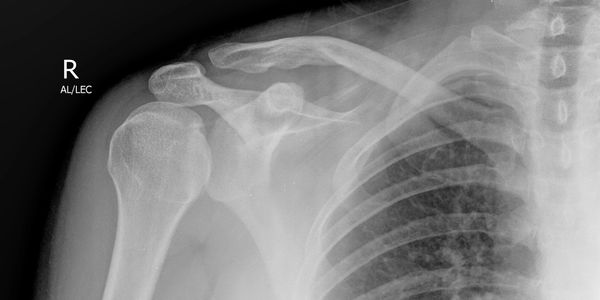

Not every greater tuberosity fracture is the same. An avulsed GT fragment (top picture) has a different mechanism (pull) to a comminuted fracture (impact) and the risk of an underlying fracture line is infinitely higher with the latter type. Turning a humeral neck fracture from undisplaced to displaced with your attempted manipulation is definitely one to avoid. There is a great case example published by Jung Ho Park in which a 74-year old man fell from a motorbike and landed on his left shoulder (impact mechanism). If you look at the initial films (above pics) the GT is not very displaced but is definitely comminuted – mechanism and GT# type now both suggest impact with risk of underlying humeral neck #. Traction/counter-traction technique had predictable results, but even using a gentle zero position may have had the same effect.

Take home message – if your patient is at higher risk of underlying pathological fracture, has an impact mechanism, or an impact fracture pattern of GT then CT to exclude an undisplaced proximal humeral fracture before you manipulate.